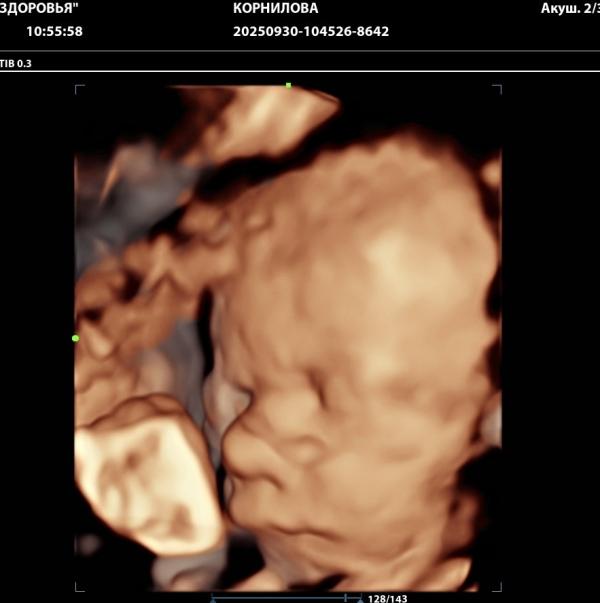

3. Парень весит 1,5 кг.

Сейчас в центре здоровья в 30 недель делают такие узи??? Не первый раз тут вижу.

Это просто круто.

Да, но только в рамках скрининга есть такая возможность) в рамках доплера просто показали малыша ))